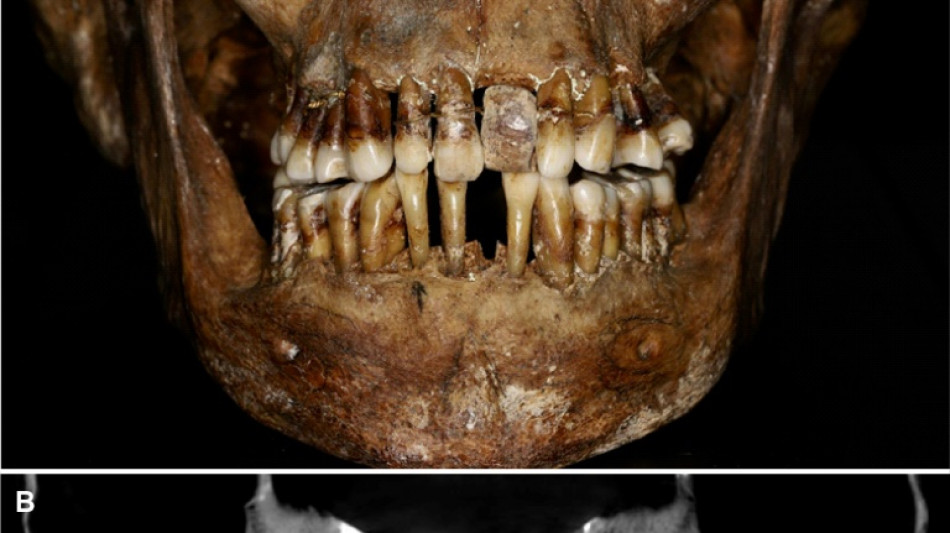

La dentition d'une aristocrate du XVIIe siècle comme marqueur social / Photo: Handout - INRAP/AFP

La sépulture d'Anne d'Alègre, morte en 1619 à l'âge de 54 ans, avait été déterrée lors d'une fouille au château de Laval, en 1988. Embaumé dans un cercueil de plomb, le squelette était particulièrement bien conservé, sa dentition aussi.

Plus de trente ans après, une équipe comprenant des archéologues et des dentistes dévoile qu'Anne d'Alègre était atteinte d'une maladie parodontale qui provoque le déchaussement progressif des dents, selon une étude parue cette semaine dans Journal of Archeological Science.

Les images radiologiques par "Cone Beam", un scanner en 3D, montrent que la patiente portait une prothèse dentaire remplaçant une incisive, soutenue par des fils d'or, ainsi qu'une ligature de contention sur des pré-molaires.

Des examens en macroscopie ont déterminé que cette prothèse était en ivoire d'éléphant, écartant la piste de l'ivoire de dents d'hippopotame, également utilisé à l'époque.